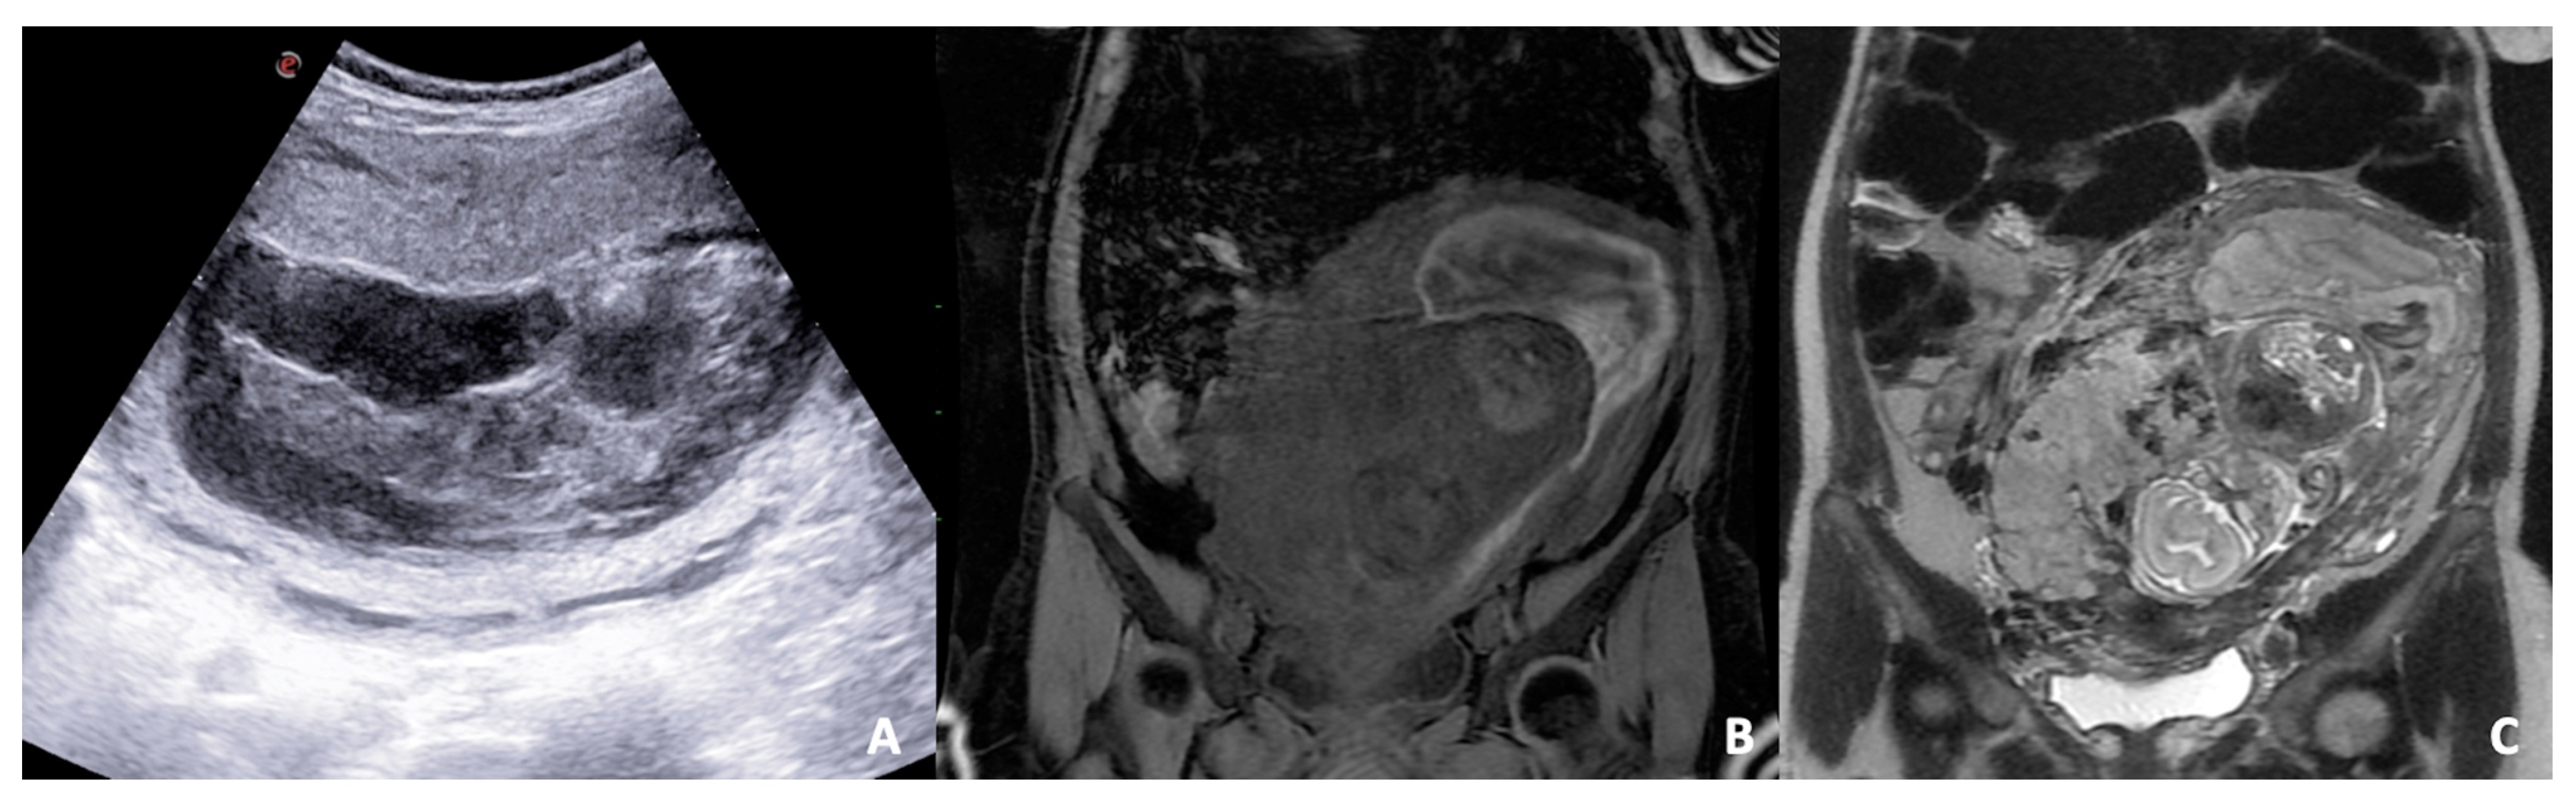

3.1. Adnexal Masses or Ovarian Cyst

- Sayasneh, A.; Ekechi, C.; Ferrara, L.; Kaijser, J.; Stalder, C.; Sur, S.; Timmerman, D.; Bourne, T. The characteristic ultrasound features of specific types of ovarian pathology (Review). Int. J. Oncol. 2015, 46, 445–458. [Google Scholar] [CrossRef] [Green Version]

- Fruscio, R.; de Haan, J.; Van Calsteren, K.; Verheecke, M.; Mhallem, M.; Amant, F. Ovarian cancer in pregnancy. Best Pract. Res. Clin. Obstet. Gynaecol. 2017, 41, 108–117. [Google Scholar] [CrossRef]